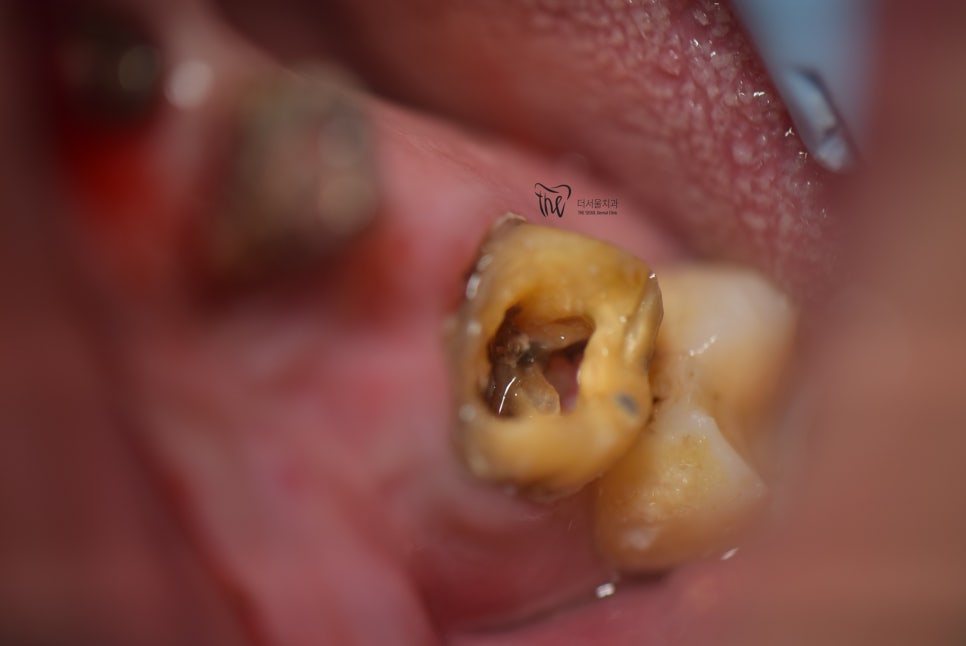

결국 이렇게, 크라운 보철 또한 같이 뜯어서

내면을 살펴 본 결과.. 이미 썩을대로

다 썩어서 문드러진 것을 보실 수 있습니다.

결국.. 3개의 임플란트 시술을 결정내립니다.